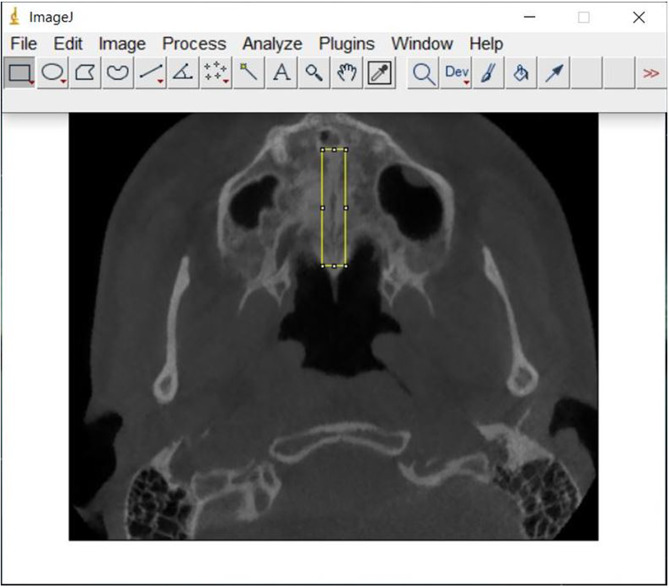

Methods: CBCT records who underwent RME and SARME between 2013 and 2024 were included in the study. CBCT axial sections taken preoperatively (T0) and after a 3-month retention period (T1) were evaluated using the MPS. Fractal Analysis (FA) method using the ImageJ program and compared between the groups.

Abstract Image